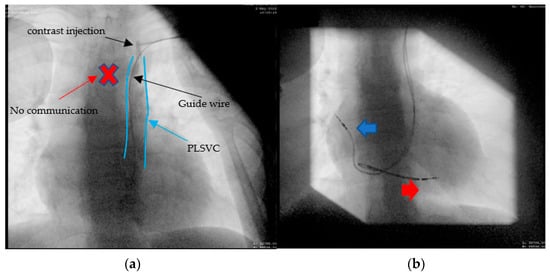

2.4. Case 4. (Type IIIB)